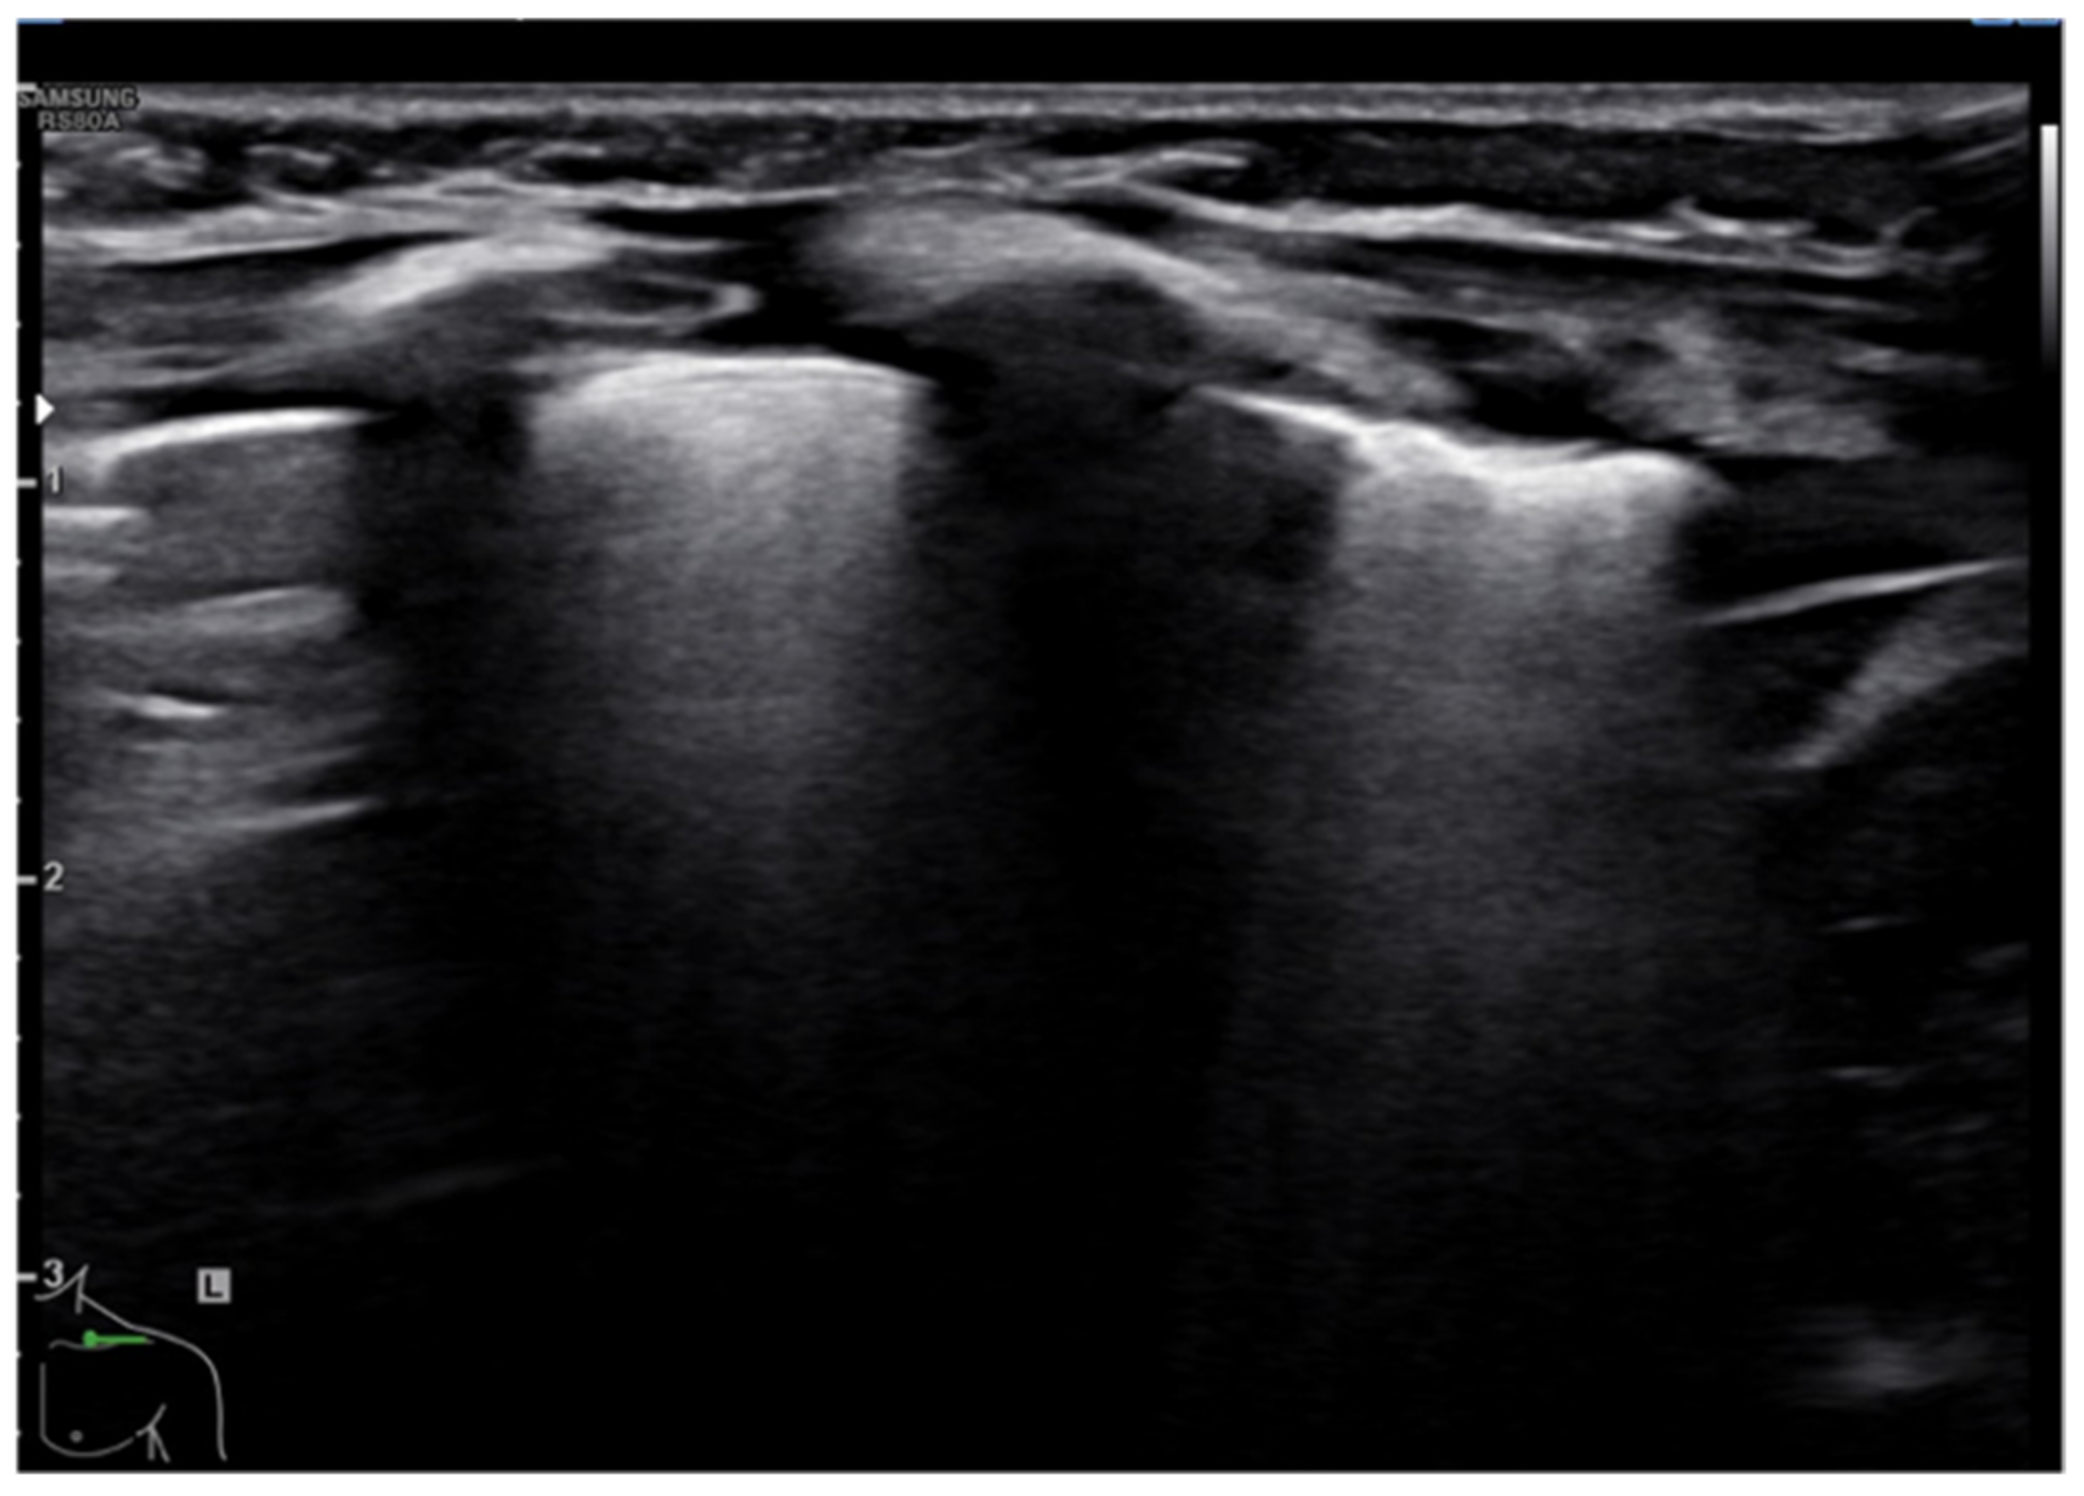

In bronchiolitis, the main ultrasound findings are: areas of subpleural consolidations defined as hypoechogenic areas with parenchymatous appearance and irregular margins, the presence of coalescent B-lines (three or more B-lines in each intercostal space) up to the “white lung” or focal presence of multiple B-lines (one or two B-lines in each intercostal space) and abnormalities of the pleural line (Figure 8 and Figure 9) [47]. Several studies demonstrated that lung ultrasound findings strictly correlate with the clinical evaluations in infants with bronchiolitis [48,49], and the 2020 consensus established LUS as a useful tool in assessing the severity of the disease [37]. Therefore, LUS could be used as support of the clinical examination in the identification of infants who may require more intensive care as supplementary oxygen or respiratory support [36].

Figure 8. Bronchiolitis. Coalescent B-lines arising from the pleural line.